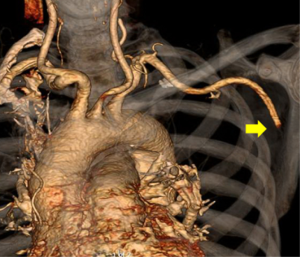

At presentation to the emergency department, he was hemodynamically stable with oxygen saturation of 92% on room air. He had a normal cardiopulmonary examination and normal cardiac biomarkers (Troponin T <0.01 and NT-BNP 284). His left upper extremity was reportedly cool with diminished radial and ulnar pulses. He had full strength and sensation in his left upper extremity and left hand. An arterial phase CT angiogram (CTA) of the chest with runoff of the left upper extremity was performed to evaluate his anatomy and look for the source of this acute arterial insufficiency. The CTA demonstrated abrupt occlusion of the left axillary artery consistent with an embolic event (Figure 4). The same study also demonstrated evidence of bilateral main pulmonary arterial embolism (Figure 5). The PERT was activated given this complex clinical presentation of PE.